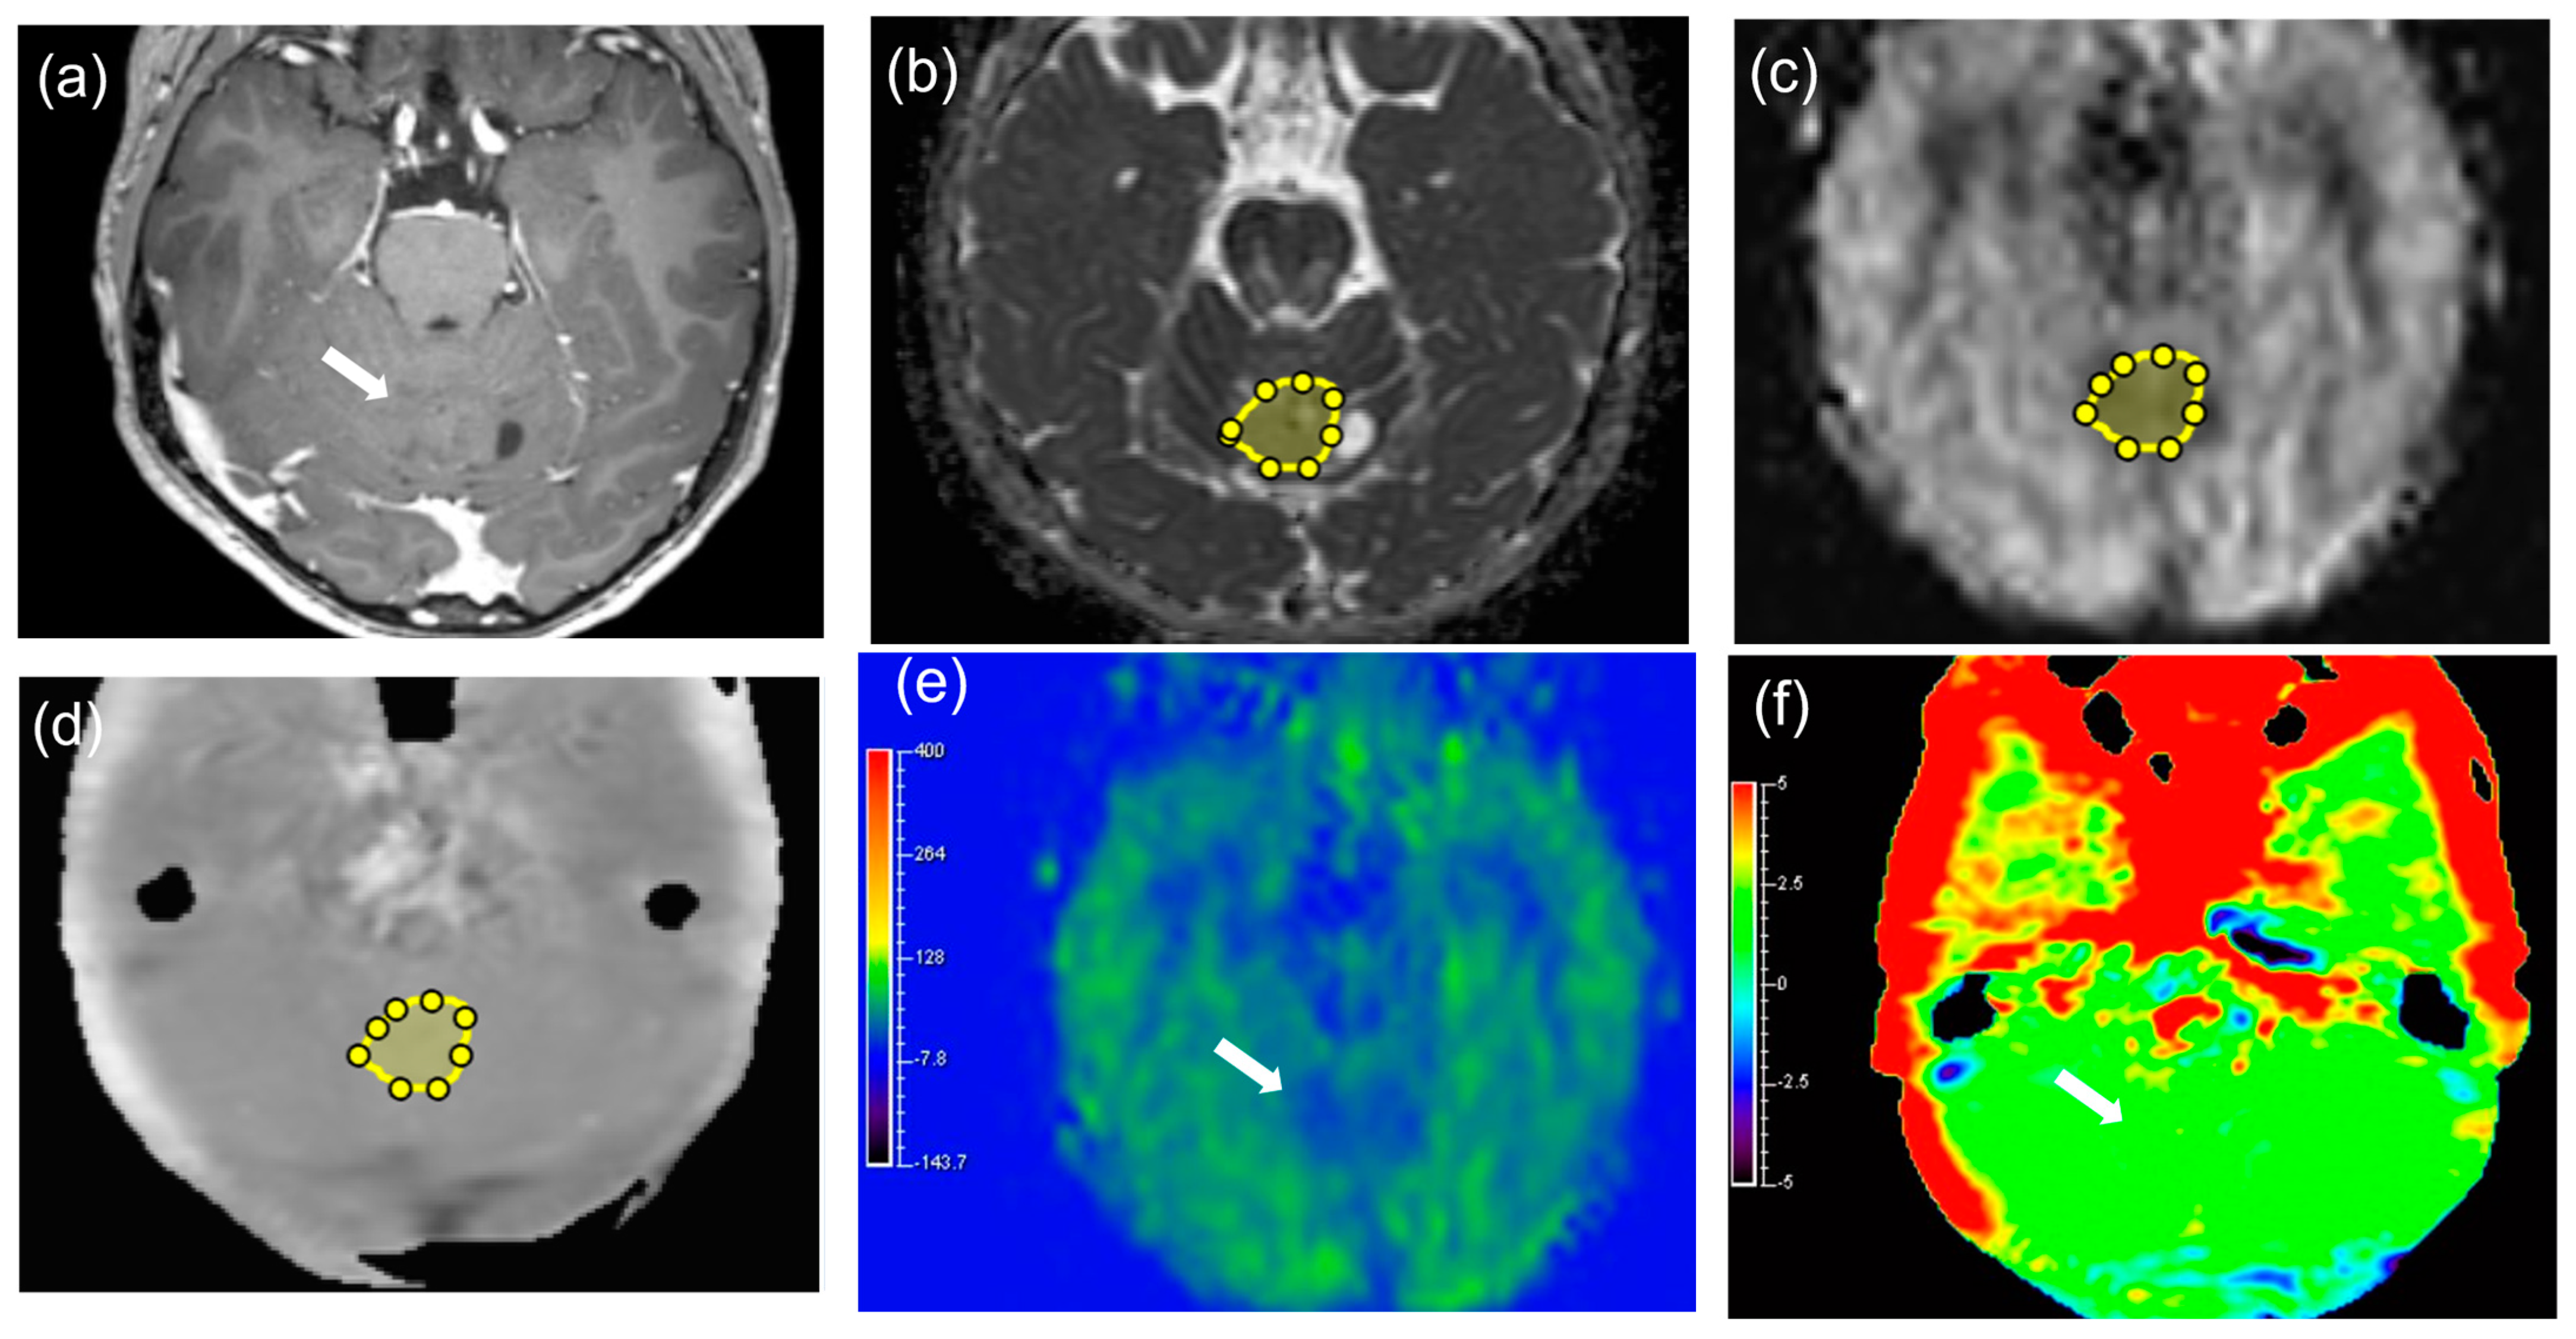

| M | 6 | 12 | F | Rt. frontal lobe | 50 | 100% resection | Paediatric-type diffuse high-grade glioma, H3-wildtype and IDH-wildtype, grade4 | Glioblastoma |

| M | 7 | 17 | M | Fourth ventricle | 44 | 70% resection | Medulloblastoma, non-WNT/non-SHH, grade 4 | Medulloblastoma |

| M | 8 | 5 | M | Fourth ventricle | 49 | 100% resection | Medulloblastoma, NOS, grade 4 | Medulloblastoma |

| M | 9 | 3 | F | Rt. lateral ventricle | 58 | 100% resection | Atypical teratoid/rhabdoid tumor, grade 4 | Atypical teratoid/rhabdoid tumor |

| M | 10 | 11 | F | Lt. basal ganglia | 50 | 80% resection | Germinoma, ICD/3 | Germinoma |

| M | 11 | 22 | M | Pineal region | 28 | 100% resection | Germinoma, ICD/3 | Germinoma |

| M | 12 | 27 | M | Pineal region | 33 | Biopsy | Germinoma, ICD/3 | Germinoma |

| M | 13 | 0 (1 month) | M | Fourth ventricle | 45 | 90% resection | Immature teratoma, ICD/3 | Immature teratoma, |

| M | 14 | 6 | M | Pineal region | 39 | Biopsy | Immature teratoma, ICD/3 | Immature teratoma |

| M | 15 | 12 | M | Suprasellar region | 40 | Biopsy | Mixed germ cell tumor, ICD/3 | germinoma and immature teratoma |

| B | 16 | 30 | F | Rt. parietal lobe | 36 | Biopsy | Astrocytoma, IDH-mutant, grade 2 | Diffuse astrocytoma without microvascular proliferation, or necrosis Homozygous deletion of CDKN2A/B was not detected. |

| B | 17 | 22 | M | Lt. thalamus~midbrain | 19 | 60% resection | Diffuse low-grade astrocytoma, NOS | Diffuse astrocytoma, IDH-wildtype without microvascular proliferation, or necrosis No TERT promoter mutation, EGFR gene amplification, or +7/−10 chromosome copy-number alterations were detected. |

| B | 18 | 30 | F | Lt. thalamus~hypothalamus | 15 | Biopsy | Diffuse low-grade astrocytoma, NOS | Diffuse astrocytoma, IDH-wildtype without microvascular proliferation, or necrosis No TERT promoter mutation, EGFR gene amplification, or +7/−10 chromosome copy-number alterations were detected. |

| B | 19 | 3 | M | Lt. temporal lobe | 23 | 100% resection | Diffuse low-grade astrocytoma, NOS | Diffuse astrocytoma IDH wildtype without microvascular proliferation, or necrosis BRAF p.V600E mutation was detected. |

| B | 20 | 6 | F | Lt. thalamus~midbrain | 27 | Biopsy | Diffuse low-grade astrocytoma, NOS | Diffuse astrocytoma without microvascular proliferation, or necrosis Histone H3 K27M mutation was not detected. |

| B | 21 | 6 | F | Lt. frontal lobe | 52 | 80% resection | Angiocentric glioma, grade 1 | Angiocentric glioma |

| B | 22 | 26 | M | Rt. thalamus~midbrain | 18 | Biopsy | Pilocytic astrocytoma, grade 1 | Pilocytic astrocytoma |

| B | 23 | 1 | M | Fourth ventricle | 51 | 70% resection | Posterior fossa ependymoma, group A, grade 2 | Ependymoma |

| B | 24 | 9 | M | Lt. lateral ventricle | 87 | 70% resection | Supratentorial ependymoma, NOS, grade 2 | Ependymoma |

| B | 25 | 10 | F | Cerebellar vermis | 26 | Biopsy | Pilocytic astrocytoma, grade 1 | Pilocytic astrocytoma |